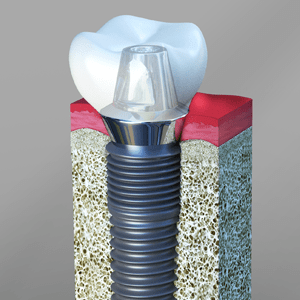

Dental Implants

Dental implant surgery is one of the procedures performed by a periodontist. The process involves restoration of a lost tooth using Titanium or Zirconium implant which replaces the lost tooth root. The surgical process involves making an incision in the gum tissues and creating a bony recess in the bone where the implant is inserted. The gum tissues are sutured after the placement of the implant and it is left to heal for a period of few months. The dental crowns are fabricated in the lab and they are fixed over the implant using an abutment. Today there are same day implants available which do not require time to heal and the crown is ready to take the load on same day.